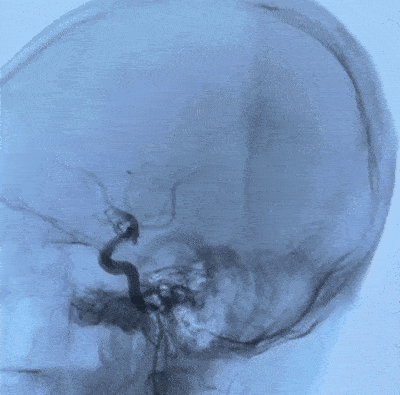

术前造影

术前进行脑血管造影,前交通开放,3D造影发现左侧颈内动脉后交通段动脉瘤。

术后造影

导丝按摩,令近远端和弯曲血管更贴壁。

术后造影可见动脉瘤囊内造影剂即刻滞留,通桥麒麟™血流导向密网支架尾端完全打开,贴壁良好,支架内血流畅通。